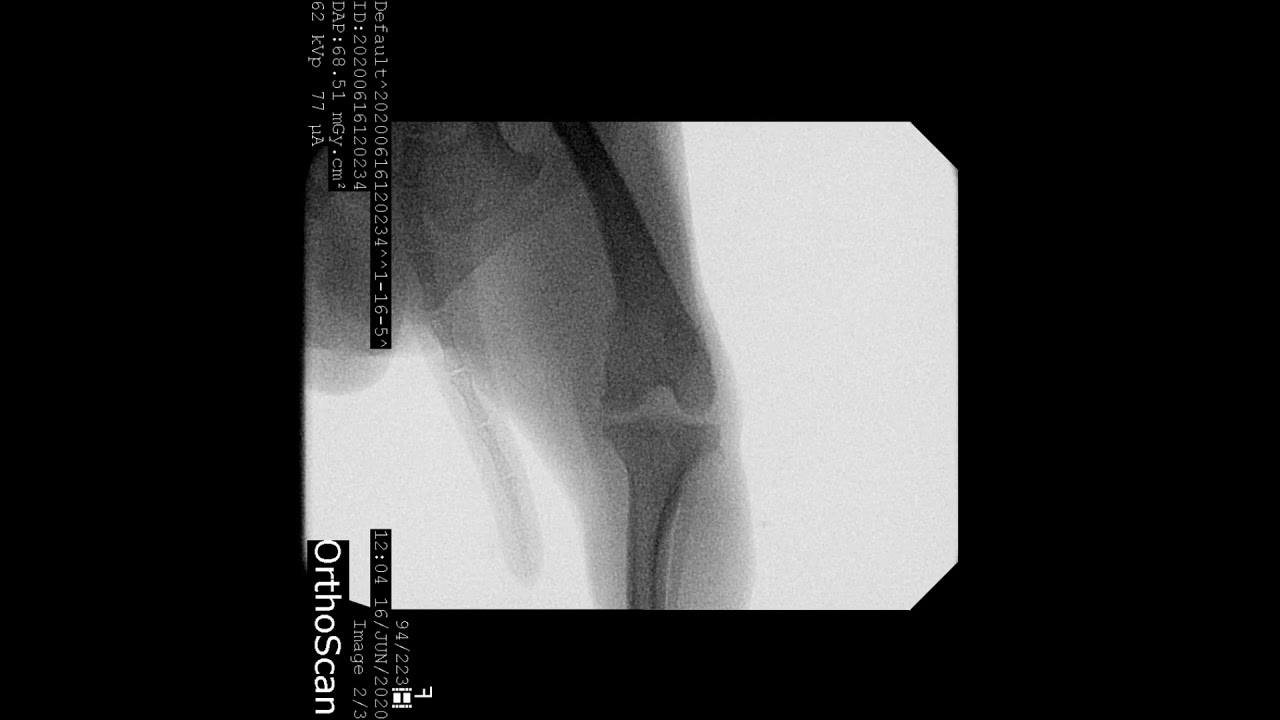

Patellar luxation (dislocation) is a condition where the knee cap rides outside the femoral groove when the knee is flexed (figure 1). The patella normally moves smoothly up and down in a deep groove. A luxating patella happens when the kneecap, or patella, which usually sits snugly in its groove on the femur (the thighbone), decides. A patella is said to be luxating—or. Patellas (kneecaps) can luxate (move. A dog's kneecap (patella) normally sits in a groove at the lower end of the thigh bone (femur) and moves up and down when the knee is flexing and. What is a luxating patella? A luxating patella is a dislocated kneecap. In a dog with luxating patella,. A trick knee in your dog is caused by an inherited deformity in the bones that allow the kneecap to move from side to side (a luxating patella).

A dog's patella (kneecap) is dislocated inward due to limb extension Where Is A Dog S Kneecap A patella is said to be luxating—or. It is an integral part of the knee joint. Patellar luxation (dislocation) is a condition where the knee cap rides outside the femoral groove when the knee is flexed (figure 1). Patellas (kneecaps) can luxate (move. A luxating patella is a dislocated kneecap. A dog's kneecap (patella) normally sits in a groove at. Where Is A Dog S Kneecap.